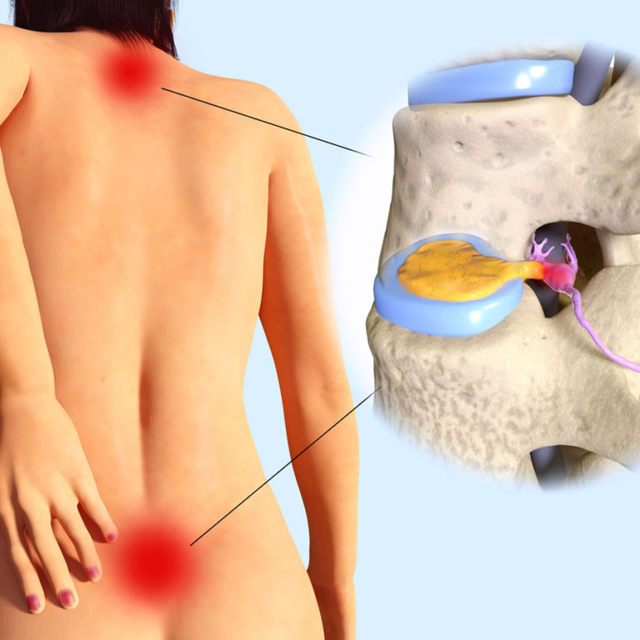

Management of disc-related pain through medications, physiotherapy, lifestyle guidance, or surgical intervention when necessary.

Evaluation and treatment of neck and lower back conditions affecting nerves, movement, and posture.